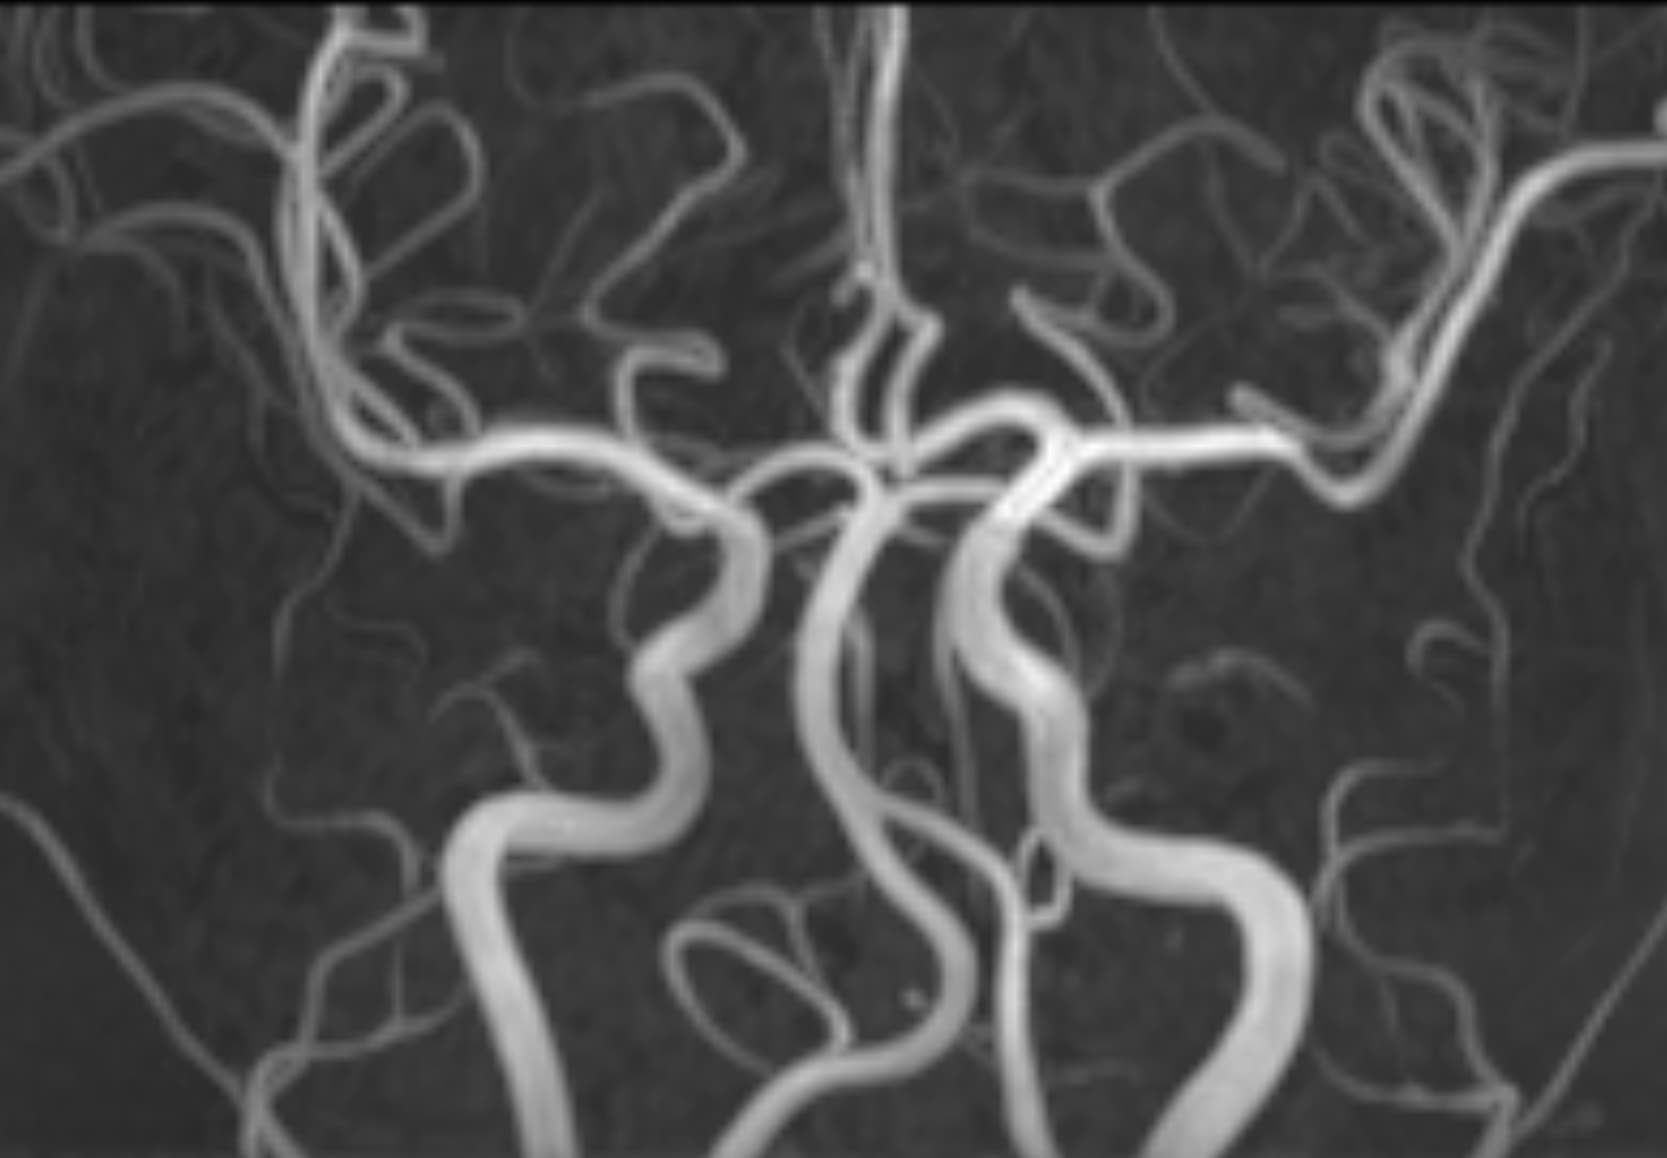

Δείτε πραγματικά παραδείγματα του SwiftMR™ σε διάφορα συστήματα MRI και ανατομικές περιοχές

Scan time 03:14

Scan time 02:07

Scan time 03:08

Scan time 1:12

Scan time 04:53

Scan time 1:46